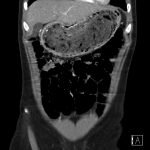

In the abdominal radiograph, a nonspecific and non-obstructive bowel gas pattern with no air-fluid level was noted, however the stomach was distended with soft tissue. The CT abdomen/pelvis revealed a distended stomach with undigested heterogeneous contents (presumed bezoar).